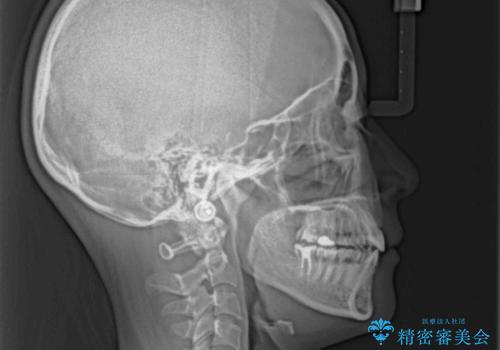

- 口元の突出感を気にして来院された患者様です。

口元を積極的に引っ込めるために、上下左右の第一小臼歯を4本抜歯することとし、ワイヤー装置による矯正治療を行うこととしました。

上下前歯がくちばしのように突出していましたが、抜歯矯正により口元が引っ込み、唇が閉じやすくなり、鼻の下の膨れた感じも解消されました。